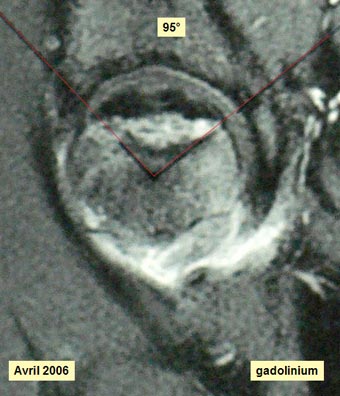

Imagerie préopératoire I.R.M.N.

Justification de la méthode Le traitement de l'ostéonécrose aseptique par autogreffe de moelle osseuse repose sur l'hypothèse que les cellules de la lignée ostéogénique dérivent d'une cellule souche initiatrice du stroma médullaire appelée CFU-F ou « Colony Forming Unit Fibroblastic ». On sait qu'il y a un appauvrissement cellulaire de la moelle osseuse dans l' ONANT. Deux techniques chirurgicales ont été proposées. La greffe de moelle osseuse pour augmenter le nombre de progéniteurs osseux situés dans la tête fémorale et dans la région trochantérienne. L'apport d'os spongieux que Steinberg a proposé de prélever au niveau de l'extrémité supérieure de la métaphyse fémorale. La question est : y a t-il à ce niveau un stock de cellules-souches suffisant ? Bien que la technique de greffe de moelle osseuse soit réservée aux stades I et II de la nécrose, nous avons proposé une intervention associant une résection de la nécrose et un comblement-greffe de la zone nécrotique à l'aide d'un composite : mélange de substitut osseux imprégné de moelle osseuse. Pourquoi ? Au stade III, contrairement au stade I et II, il n' y a pas de réversibilité spontanée possible, il ne paraît donc pas suffisant de se limiter à l'injection de la moelle osseuse sans nettoyer cette cavité en excisant la zone de nécrose. Dans le but de limiter l'écrasement responsable de la perte de la sphéricité de la tête fémorale, il est logique d'apporter « in situ » un matériau biologique mécaniquement résistant qui comble l'espace vide conjointement à l'adjonction du facteur biologique. La justification de cette proposition tient enfin au fait que l'étendue de la nécrose (95°) rend l'ostéotomie inter-trochantérienne très problématique sur le plan technique. En cas d'échec du comblement-greffe, il n'y aura aucune difficulté supplémentaire pour réaliser cette ostéotomie.